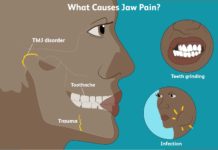

Tooth Pain: Causes, Symptoms, and Treatment

Tooth pain usually happens when nerves in the root of a tooth or surrounding a tooth are irritated. Tooth infection, decay or loss of...

8 Things You Should Know Before You Get Dental Implants

People who suffer from missing teeth are at present considering a tooth implant as a viable option instead of going for temporary fixtures that...